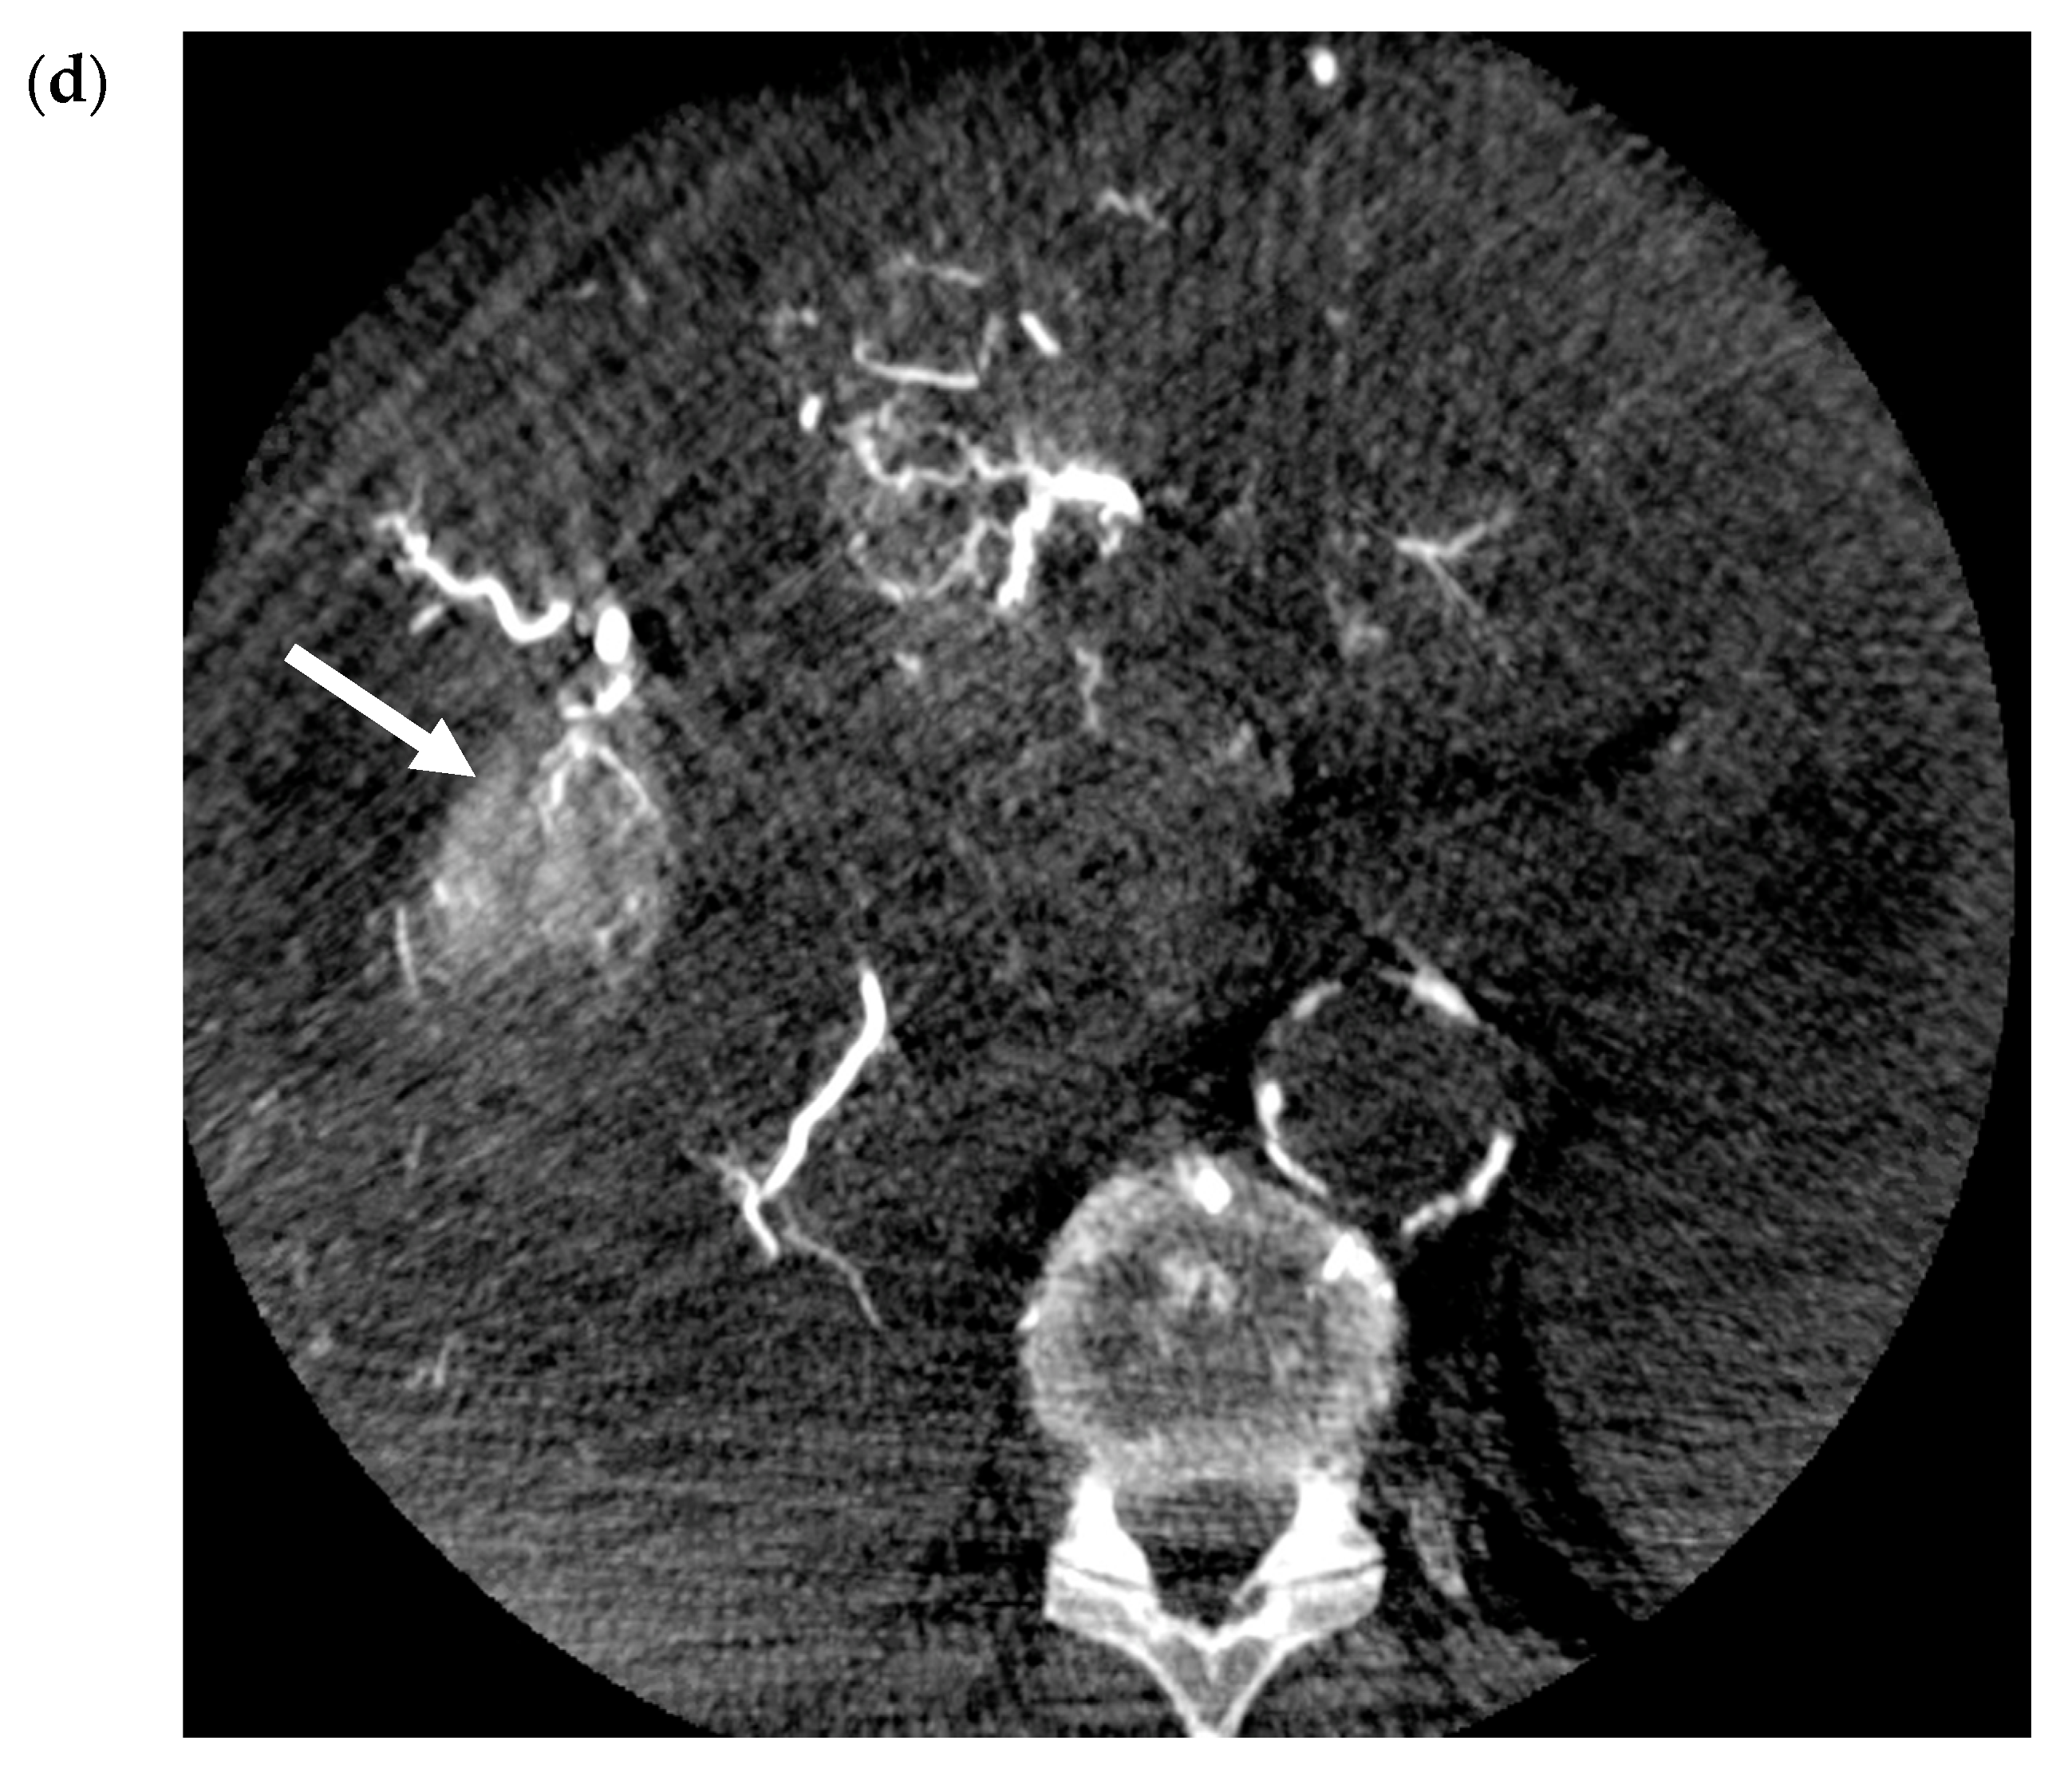

- Ogata, S.; Belghiti, J.; Farges, O.; Varma, D.; Sibert, A.; Vilgrain, V. Sequential arterial and portal vein embolizations before right hepatectomy in patients with cirrhosis and hepatocellular carcinoma. Br. J. Surg. 2006, 93, 1091–1098. [Google Scholar] [CrossRef]

- Yoo, H.; Kim, J.-H.; Ko, G.-Y.; Kim, K.W.; Gwon, N.I.; Lee, S.-G.; Hwang, S. Sequential Transcatheter Arterial Chemoembolization and Portal Vein Embolization versus Portal Vein Embolization Only before Major Hepatectomy for Patients with Hepatocellular Carcinoma. Ann. Surg. Oncol. 2010, 18, 1251–1257. [Google Scholar] [CrossRef]